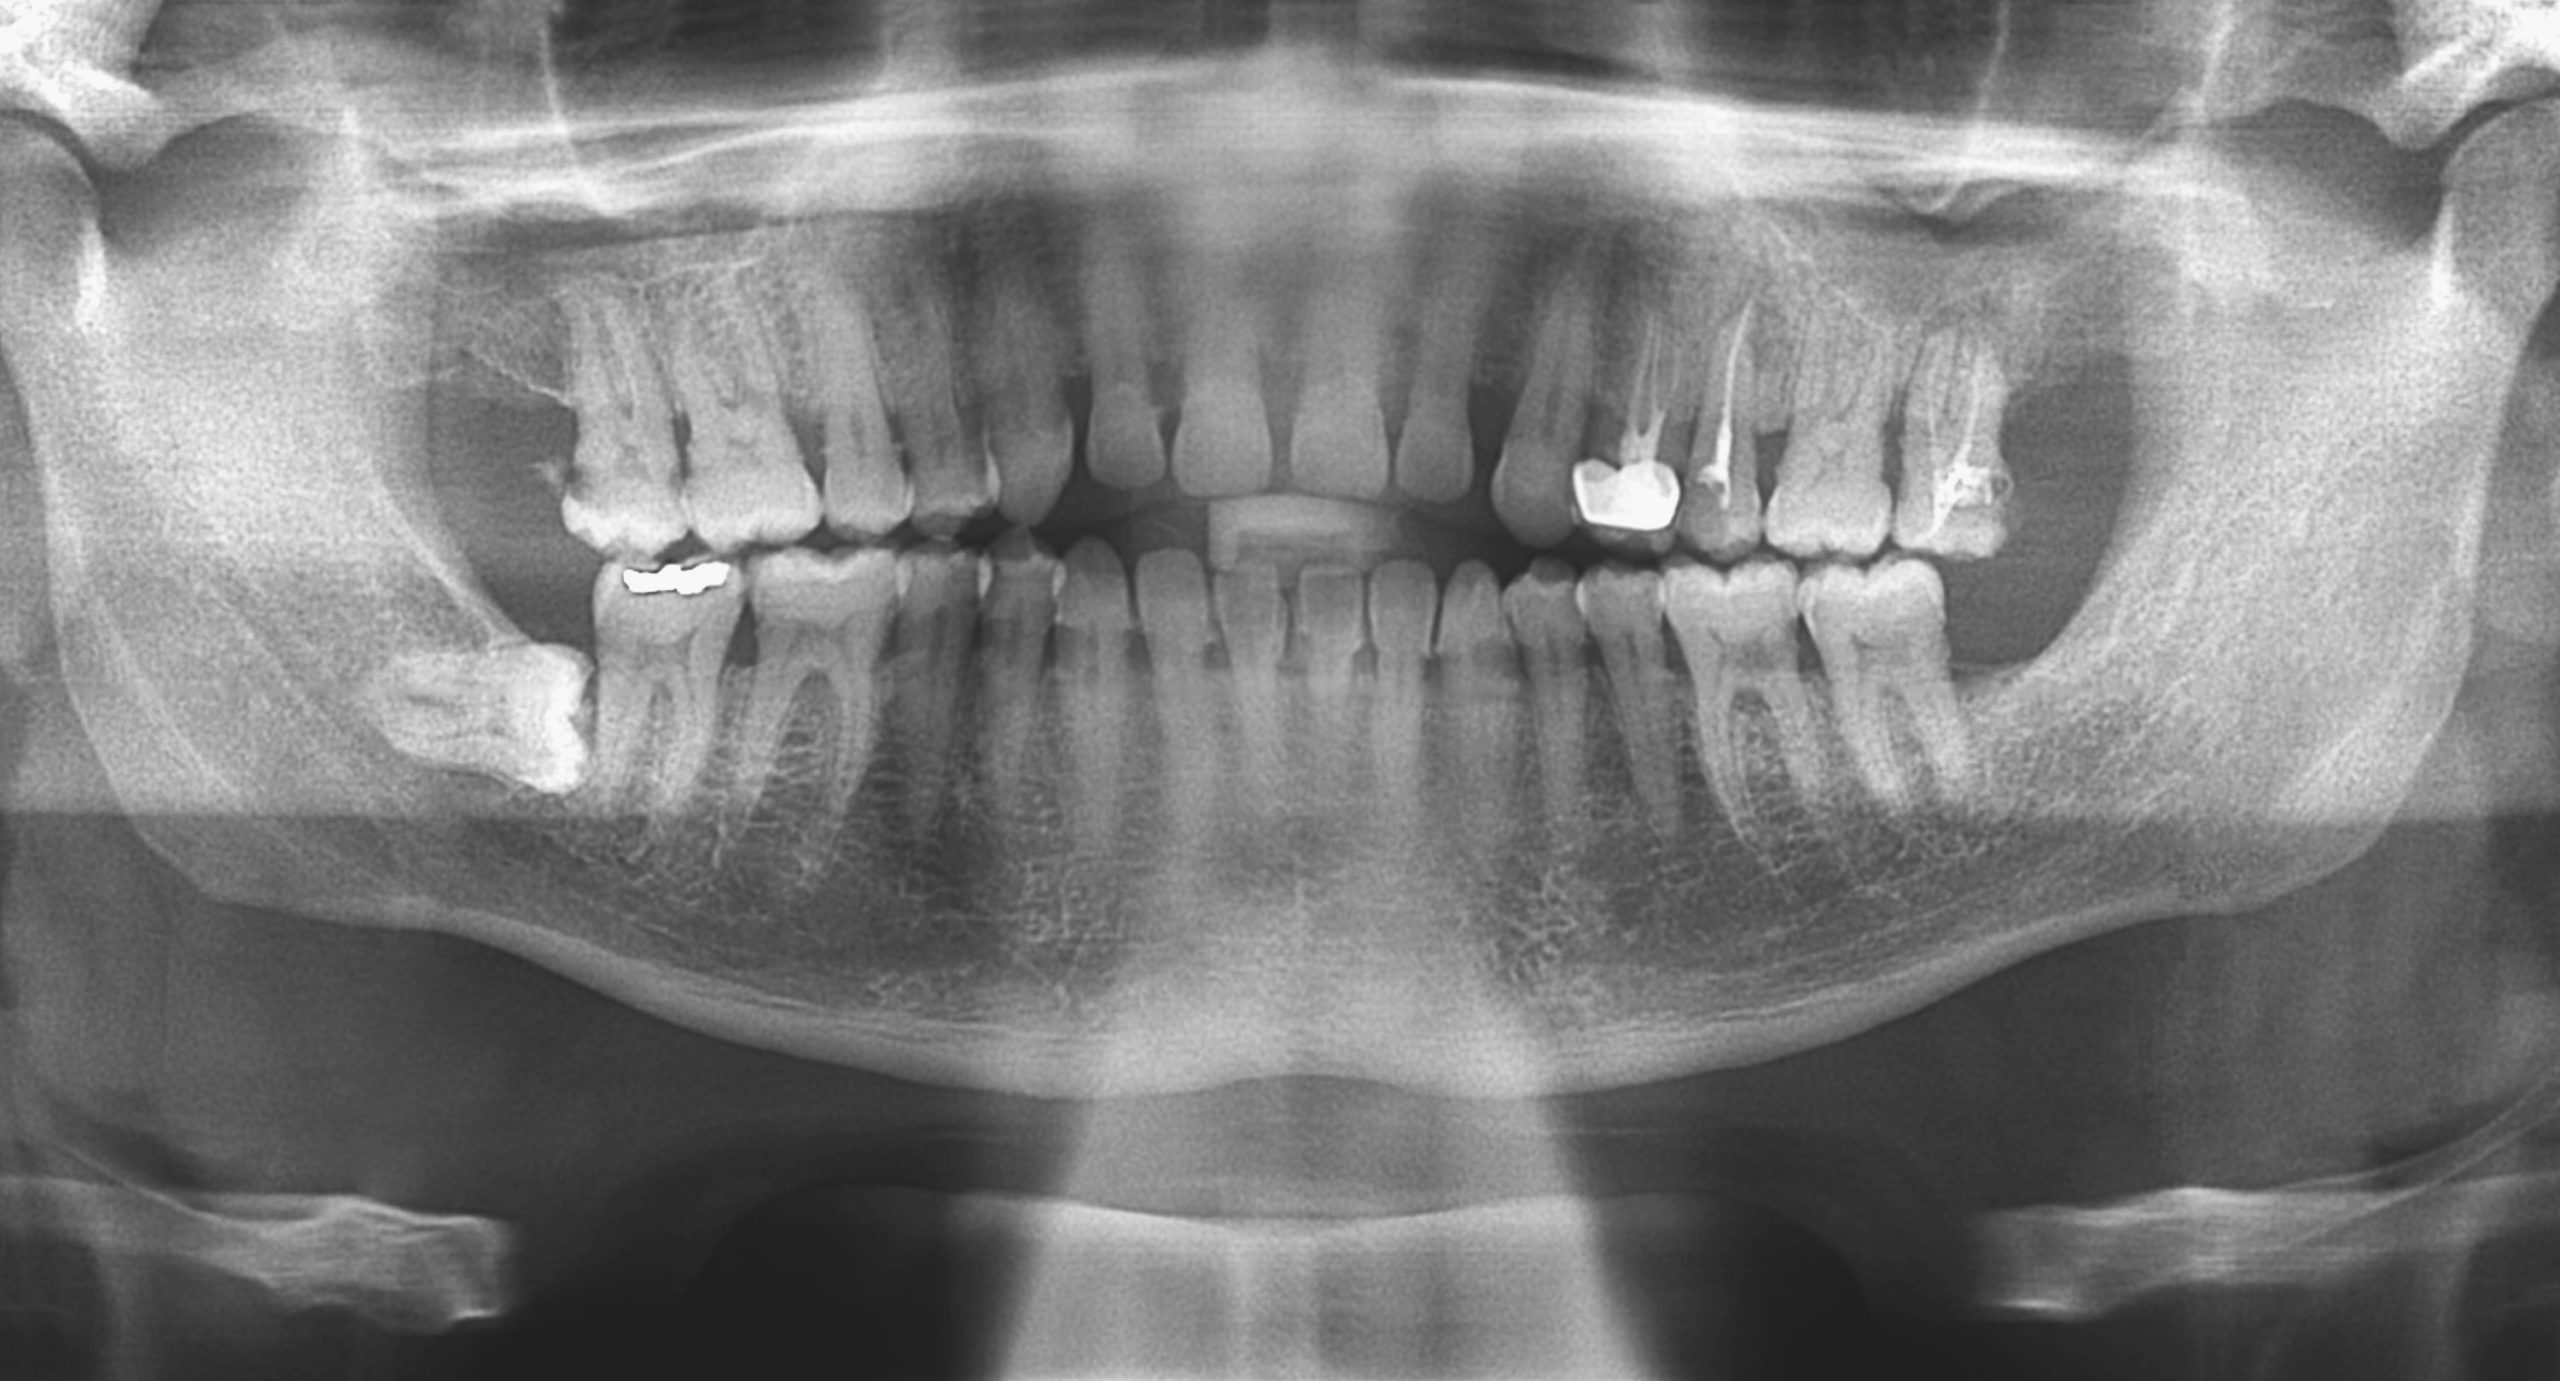

dental xrays Panoramic xray Hancock Village Dental Dentist Dental X Rays Third Trimester Dental radiographs are considered to be safe during pregnancy. Unfortunately pregnant patients are not immune to developing dental pain or infections, and so there will be times when. 1 in addition to regular visits to your dentist, you. Oral health care, including having dental radiographs taken and being given local anesthesia, is safe at any point during pregnancy. 1, 2. Dental X Rays Third Trimester.

Panoramic Dental Xrays Dataset Ninja Dental X Rays Third Trimester Unfortunately pregnant patients are not immune to developing dental pain or infections, and so there will be times when. 1 in addition to regular visits to your dentist, you. 1 the american college of obstetricians and gynecologists recommends. Oral health care, including having dental radiographs taken and being given local anesthesia, is safe at any point during pregnancy. Dental radiographs. Dental X Rays Third Trimester.